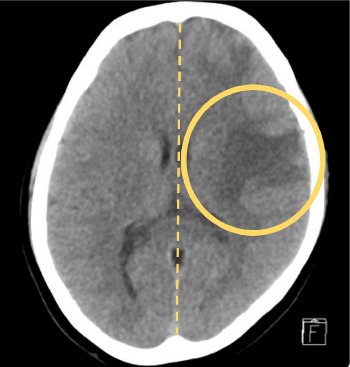

结核(TB),由结核分枝杆菌引起,主要影响肺部,但可以涉及几乎任何器官系统,表现为肺外结核。虽然结核病相关的高凝性和静脉血栓栓塞是公认的,但这种表现仍然不常见,诊断上具有挑战性,特别是在没有经典症状的情况下。病例介绍:我们报告一个24岁的免疫功能正常的女性谁最初提出无痛右侧颈部肿胀。影像显示右侧颈内静脉(IJV)出现急性血栓,原因不明。进一步检查显示纵隔淋巴结肿大坏死,怀疑为淋巴瘤。然而,患者后来出现癫痫发作,随后的神经影像学显示多发性颅内环增强病变。最终,纵隔镜淋巴结活检证实坏死性肉芽肿性炎症,结核聚合酶链反应(PCR)阳性,与弥散性结核累及血管和中枢神经系统一致。患者开始接受抗结核治疗、抗凝治疗和辅助皮质类固醇治疗,并安排多学科随访。讨论:本病例强调了结核病引起的高凝血性是孤立静脉血栓形成的潜在原因,并强调了结核病模拟恶性肿瘤时的诊断挑战。它还强调了即使在没有肺部症状的情况下,在鉴别诊断不明原因血栓形成和颅内病变时考虑结核病的重要性。结论:临床医生应在非典型血栓形成事件中保持对肺外结核的高度怀疑。早期组织诊断和多学科方法是有效管理和良好结果的关键。

Introduction: Tuberculosis (TB), caused by Mycobacterium tuberculosis, primarily affects the lungs but can involve virtually any organ system, manifesting as extrapulmonary TB. While TB-related hypercoagulability and venous thromboembolism are recognized, such presentations remain uncommon and diagnostically challenging, especially in the absence of classical symptoms. Case Presentation: We report the case of a 24-year-old immunocompetent female who initially presented with painless right-sided neck swelling. Imaging revealed an acute thrombus in the right internal jugular vein (IJV), with no clear underlying cause. Further evaluation showed enlarged necrotic mediastinal lymph nodes, raising suspicion for lymphoma. However, the patient later developed a seizure episode, and subsequent neuroimaging revealed multiple intracranial ring-enhancing lesions. Ultimately, mediastinoscopic lymph node biopsy confirmed necrotizing granulomatous inflammation, with a positive TB polymerase chain reaction (PCR), consistent with disseminated TB involving both vascular and central nervous systems. The patient was started on antitubercular therapy, anticoagulation, and adjunctive corticosteroids, with multidisciplinary follow-up arranged. Discussion: This case highlights TB-induced hypercoagulability as a potential cause of isolated venous thrombosis and underscores the diagnostic challenges when TB mimics malignancy. It also emphasizes the importance of considering TB in the differential diagnosis of unexplained thrombosis and intracranial lesions, even in the absence of pulmonary symptoms. Conclusion: Clinicians should maintain a high index of suspicion for extrapulmonary TB in atypical thrombotic events. Early tissue diagnosis and a multidisciplinary approach are key to effective management and favorable outcomes.